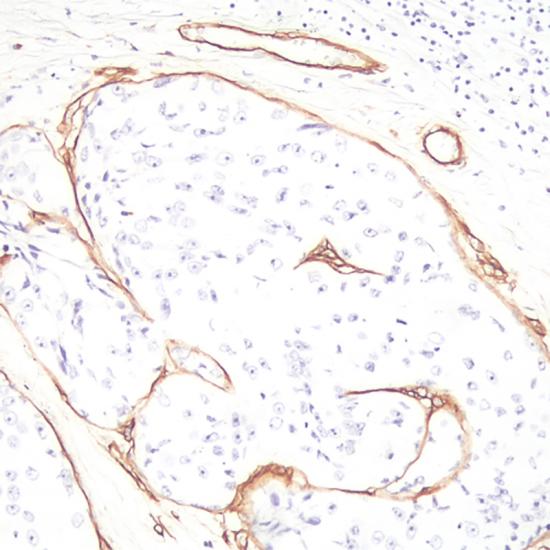

Laminin

• 陽性部位:

基底膜

• 陽性對照:

乳腺癌

層粘連蛋白是細(xì)胞外基底膜的重要組成部分,分布于基底膜和細(xì)胞外基質(zhì)、成纖維細(xì)胞、內(nèi)皮細(xì)胞和平滑肌細(xì)胞分泌層粘連蛋白。腫瘤的浸潤和轉(zhuǎn)移與其遭到破壞相關(guān),該抗體可用于標(biāo)記基底膜,有助于觀察腫瘤周圍基底膜的分布及其變化,間接提示腫瘤的分化程度和浸潤情況。